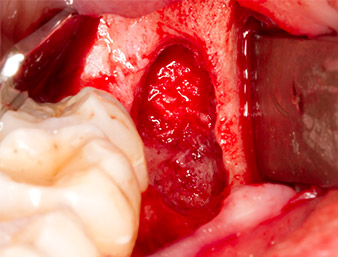

After block and local anaesthesia, the operating site was opened up and the soft tissue exposed for buccal retromolar access (Fig. 3).

The tissue above the root remnant was not completely ossified and consisted for the most part of granulation tissue modified by inflammation (Fig.4).